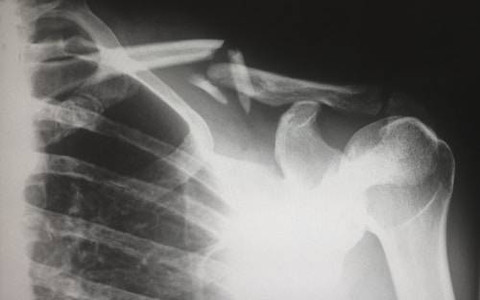

Sendi peluru merupakan jenis sendi untuk berbagai gerakan ke segala arah, termasuk gerak memutar. Sendi peluru memiliki rongga sendi dengan tulang yang ujungnya membulat (seperti bola).